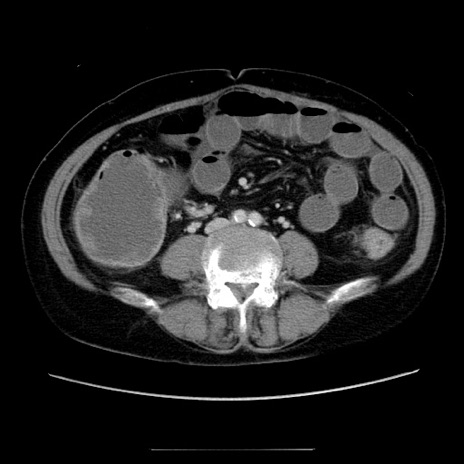

冠状断像

【症例】70歳代女性

【主訴】お腹が張る

【現病歴】1週間くらい前から腹部膨満の自覚あり。昨日夜から増悪したため、本日救急外来受診。

【身体所見】意識清明、BT 36.5℃、BP 165/106mmHg、HR 80bpm、SpO2 98%、腹部:膨満、軟、自発痛・圧痛なし、触診にて不快感あり、腸蠕動音:減弱

【データ】WBC 12600、CRP 1.04